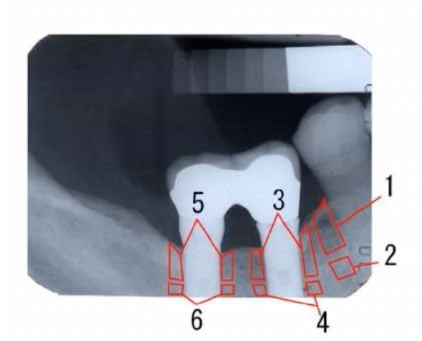

インプラント8 年経過症例の歯槽骨骨密度

- 領域

- 歯槽骨骨密度

- 1

- 89.7

- 2

- 147.4

- 3

- 111.8

- 4

- 133.1

- 5

- 133.5

- 6

- 131.1

領域1.3の歯槽骨骨密度が低下しているので

インプラント周囲炎が疑われる -

インプラント周囲炎の早期対応ができる